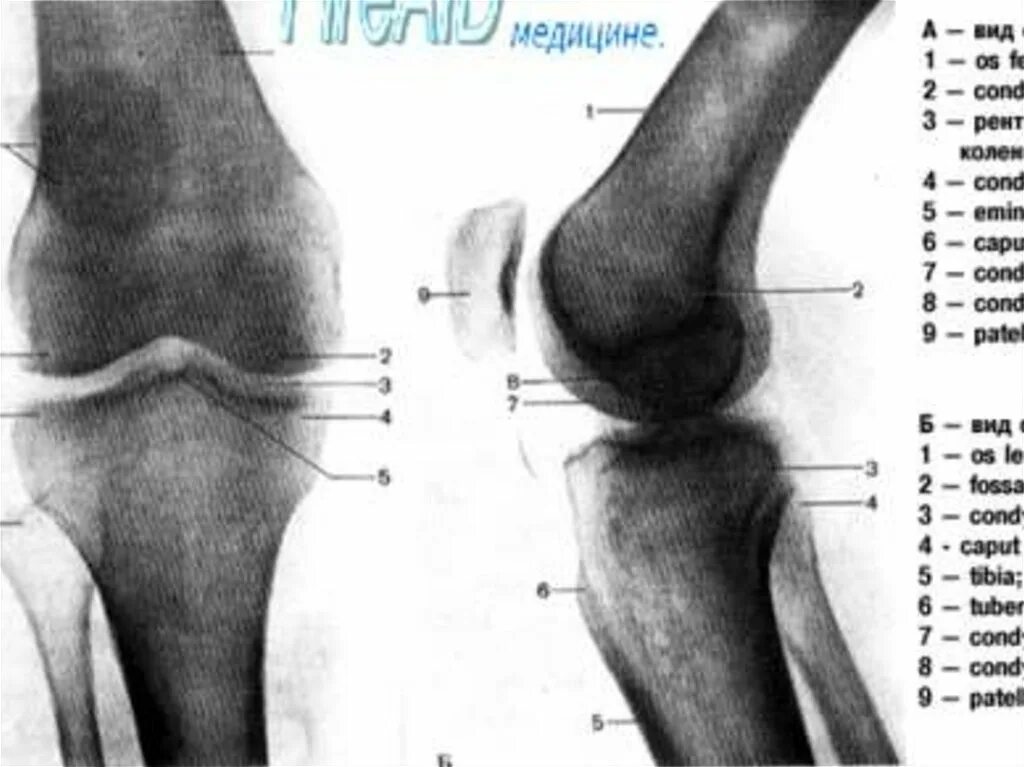

Суставная щель коленного сустава норма